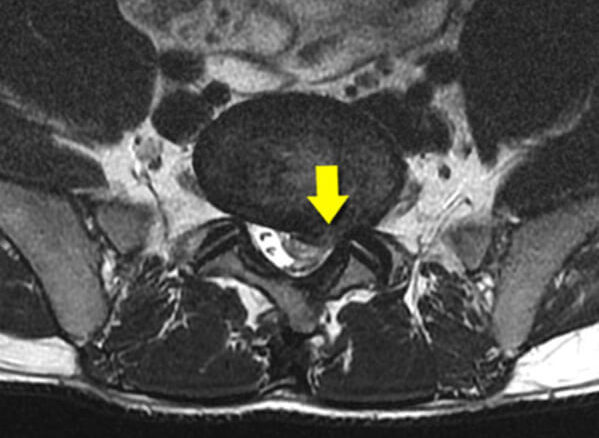

– MRI. Obrazowanie metodą rezonansu magnetycznego (MRI) pozwala lekarzom czulej i dokładniej oceniać nerwy rdzeniowe i anatomię, w tym wysokość dysków, stopień ich nawodnienia i konfigurację.

RYS.2. Duża przepuklina dokanałowa L5-S1.